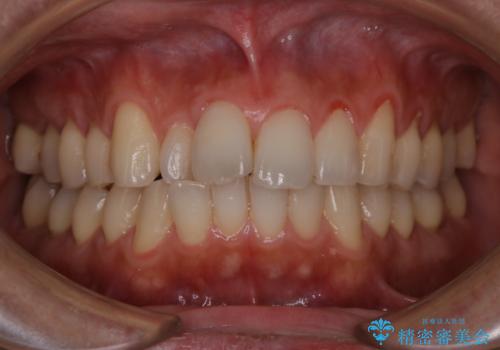

PMTCで清潔感ある口元に

PMTCで見た目を綺麗に